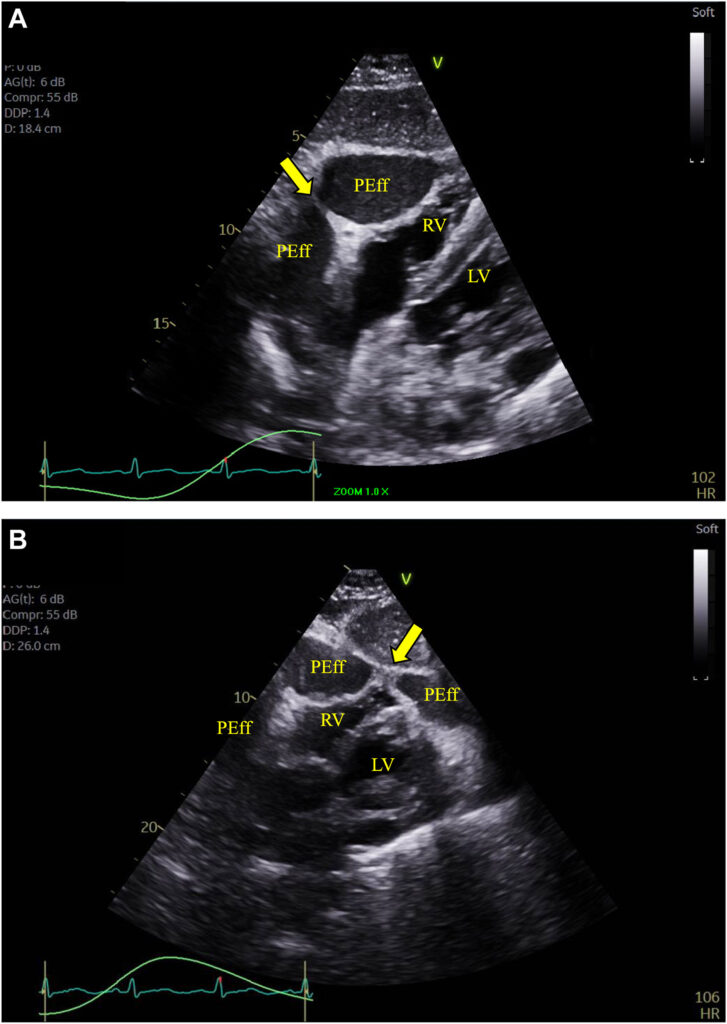

Um ecocardiograma foi novamente realizado e um importante derrame pericárdico foi documentado, contudo com aspecto multiloculado resultando em compressão de todas as 4 câmaras cardíacas.

Havia colapso diastólico da região apical e da parede lateral do ventrículo esquerdo, além do colapso do VD.

Também foi observado um espessamento do pericárdio (4 mm) com tethering da parede livre do VD e da parede lateral do VE caracterizado pela ausência da movimentação tipo deslizamento entre os folhetos parietal e visceral do pericárdio.